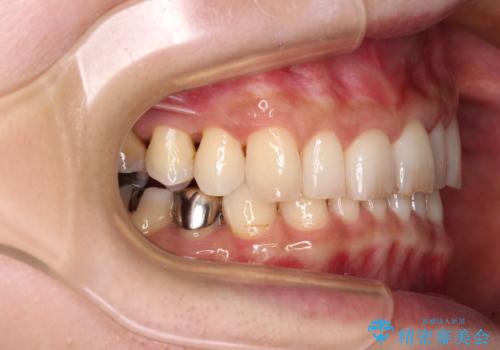

- 奥歯が咬めないくらいに痛いとのことで来院された患者様です。

痛みの強い歯は、歯髄組織が強い炎症を起こしており、神経を取り除く必要であったため、速やかに根管治療を行いました。

その後、オールセラミッククラウンにて補綴治療を行う予定でしたが、処置した歯以外にも治療が必要と思われる歯があったり、デコボコした歯列も気になるとのことで、患者様希望によりインビザラインにてマウスピース矯正を行うこととしました。

咬合力が非常に強く、全体的に歯が擦り減っている状態であったので、理想的な咬み合わせを達成することは難しく、また咬合力が強い方のマウスピース矯正は、思い通りに動かないことがあるため、ワイヤー矯正の方が望ましいように思えました。